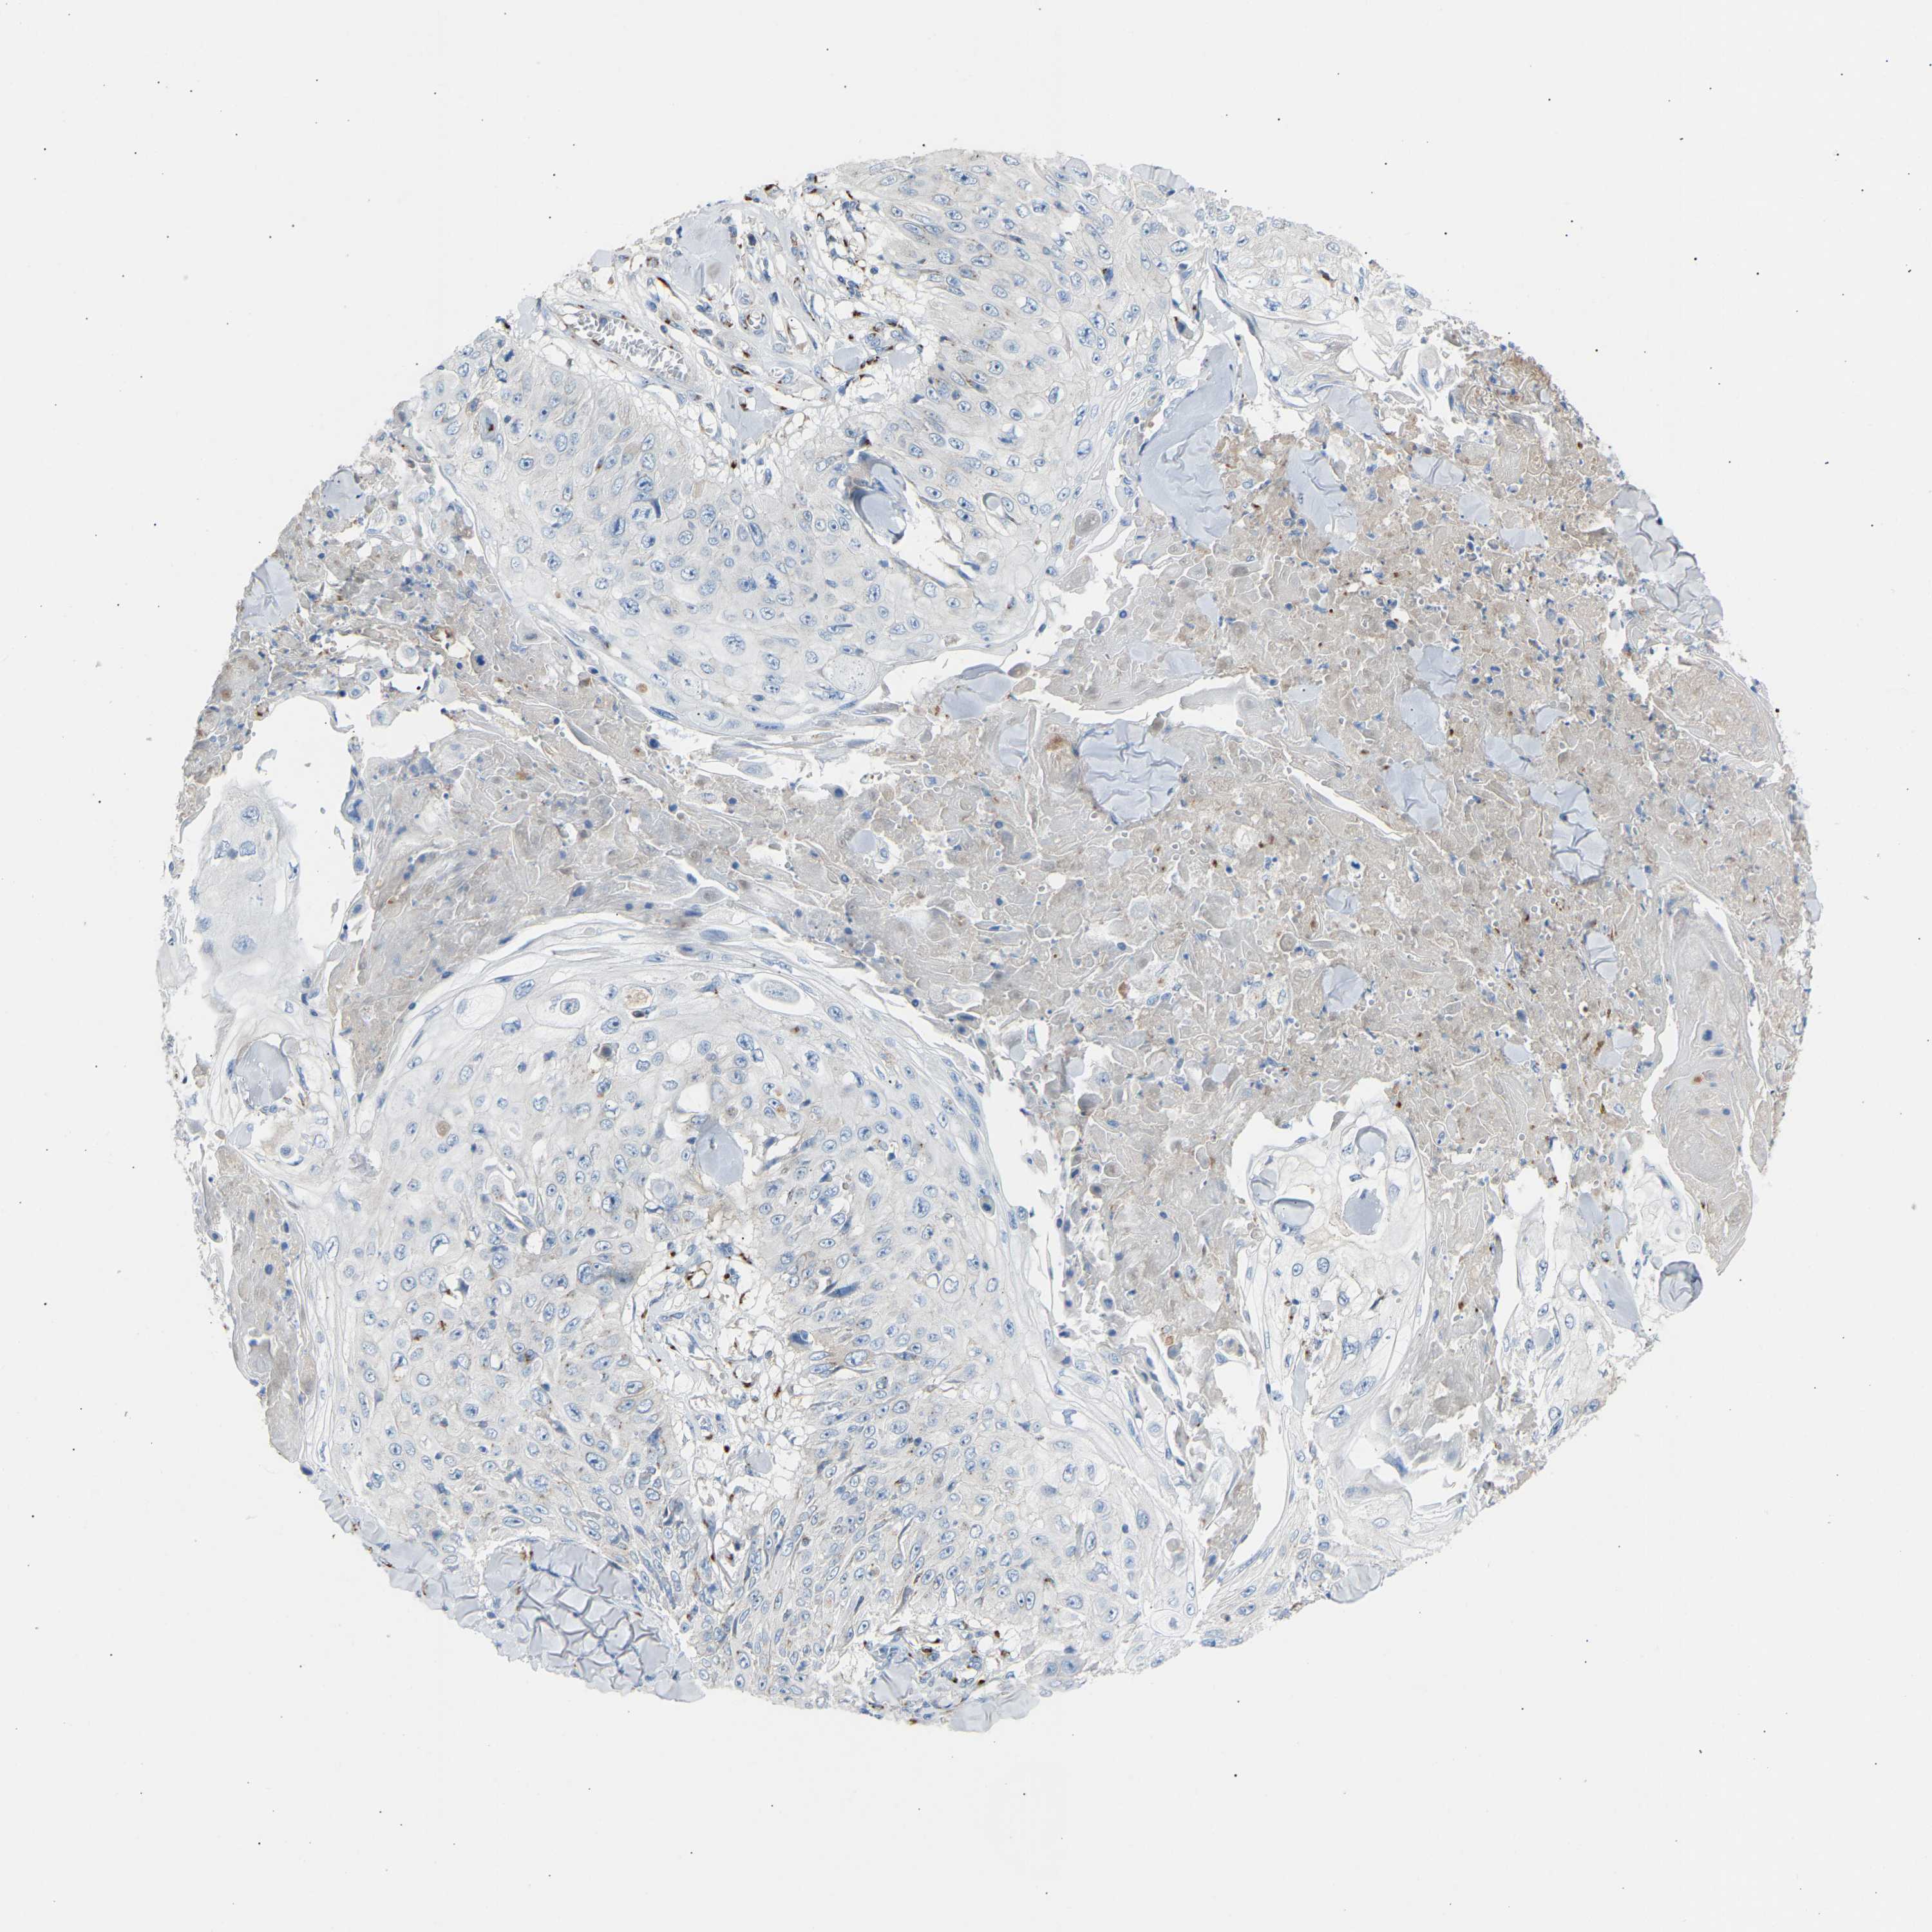

SKIN CANCER - Protein expressioni

A mouse-over function shows sample information and annotation data. Click on an image to view it in a full screen mode. Samples can be filtered based on level of antibody staining by selecting one or several of the following categories: high, medium, low and not detected. The assay and annotation is described here.

Each image is clickable and will lead to virtual microscopy that enables deeper exploration of all samples and also displays staining intensity scores, fraction scores and subcellular localization as well as patient and tissue information for each sample.

Antibody HPA020060

Squamous cell carcinoma, NOS